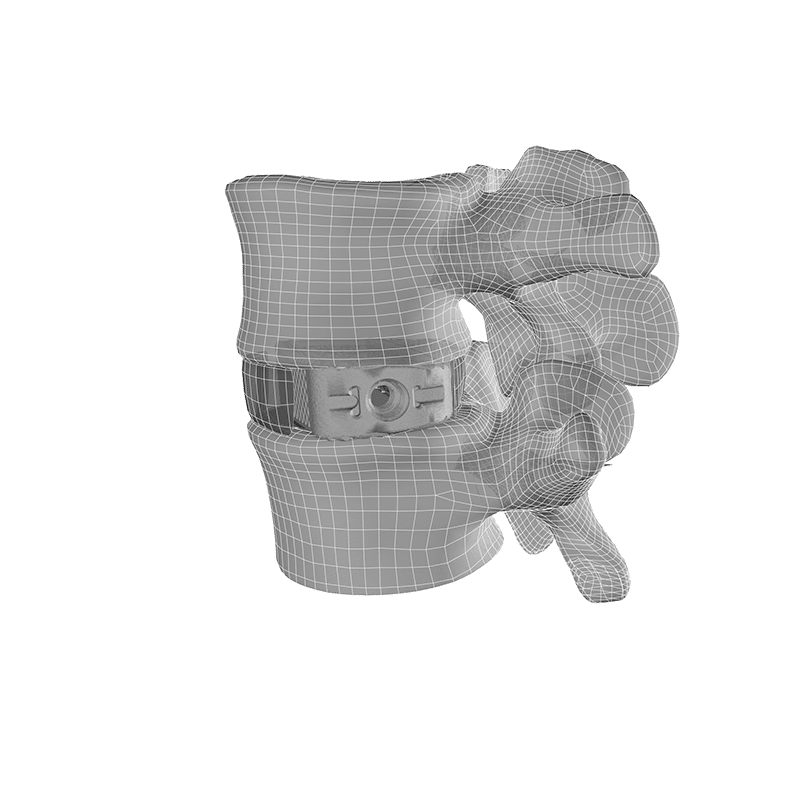

F3D Lateral Interbody

The F3D Lateral interbodies leverage the benefits of Mimetic Metal® technology which emulates key characteristics of natural bone to provide an optimal structure and environment for healing.

- Optionally attach to the Oro™ Lateral Plate

- Unique trapezoidal geometry for precise anatomical fit